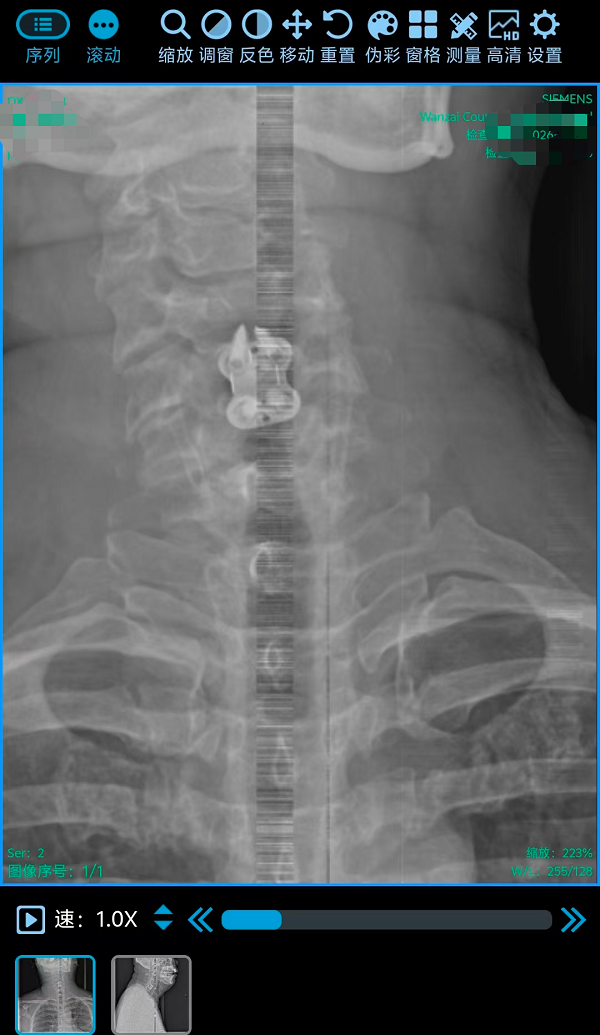

2. 为颈椎间盘巨大突出致肢体不全瘫患者行颈椎前路椎间盘切除融合内固定术(ACDF)(四级手术),该术式通过颈部前方的天然解剖间隙到达病变节段,在彻底解除脊髓和神经根压迫的同时,重建了颈椎的生理曲度和稳定性。手术团队凭借丰富的经验和精细的操作,在方寸之间精准完成了减压、植骨与内固定,有效避免了重要神经血管的损伤。

三台手术均顺利完成,患者术后恢复良好,标志着我院脊柱疾病微创化、精准化治疗迈上新台阶。